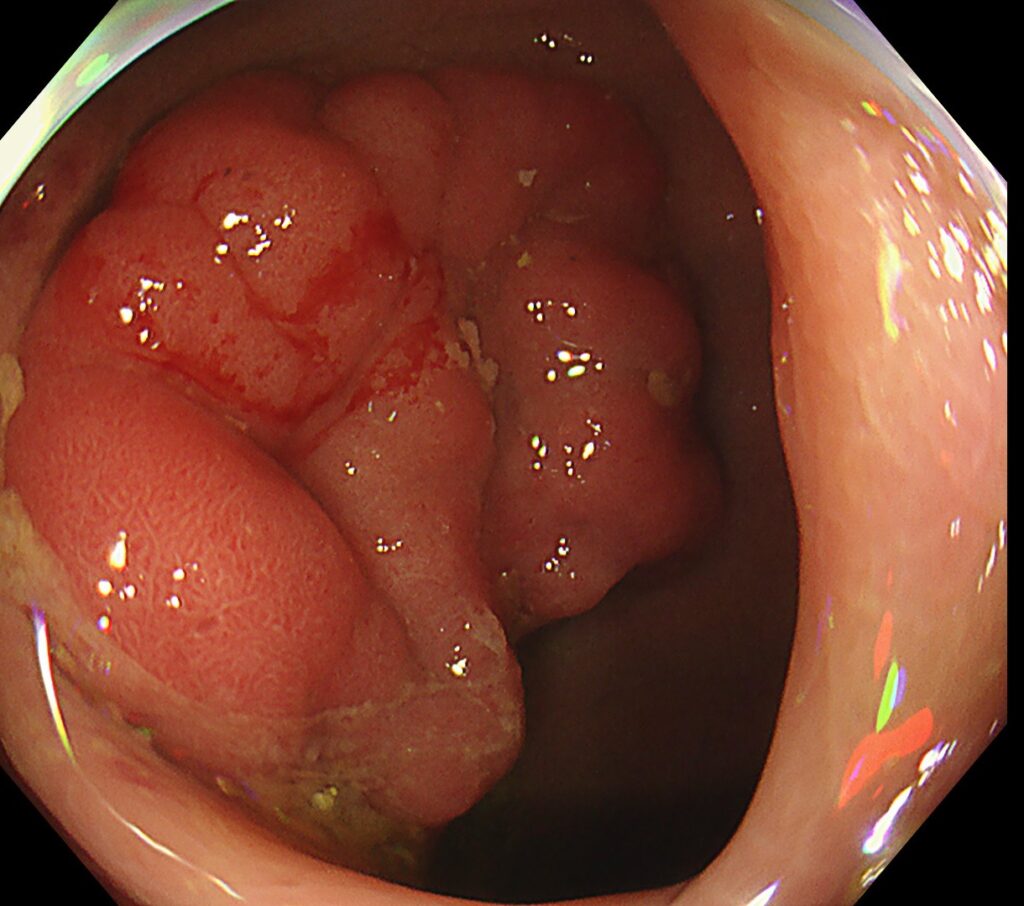

肛門から内視鏡を入れてすぐの下部直腸に、隆起性病変を認めます。

送気・脱気で腫瘍の硬さを確認してみると、浸潤癌らしき所見は認めず。

しっかり、空気を入れて、全体像を確認すると、内腔を1/4占めていることがわかります。